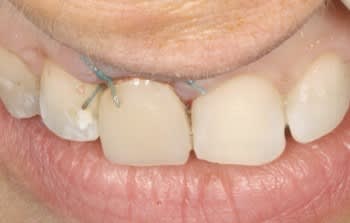

Ci joint cas avec membrane résorbable laissée exposée volontairement ( technique Bio coll proposée par Anthony G. Scar dans les années 2000 remis au gout du jour par tarnow en 2006 ).

Celà ne marche pas avec toutes les membranes...

fig 1 coupe tomo Jo

fig 2 vue clinique ( léger décalage des collets entre 11 et 21 )

fig 3 exo

fig 4 pose membrane résorbable + os xénogène

fig 5 membrane suturée

fig 6 réouverture J0 + 6mois

fig 7 vue clinique J0 + 2ans ( Prothèse Dr G.D 31 )

fig 8 vue clinique JO + 5ans (léger décalage des collets entre 11 et 21 comme à l'origine)